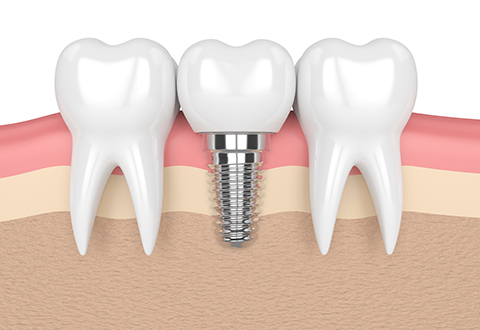

임플란트란 치아가 상실되었을 때 사용 가능한 치아 보철물로 자연치아의 90~95%의 기능으로 사용이 가능하다고 해요. 특수금속으로 만들어진 인공치아를 상실된 치아 부위의 잇몸뼈에 식립하고 그 위에 인공치아를 장착해 수복하는 치료방법으로 본래 자기 치아와 가장 유사한 형태와 기능을 한다고 해요.

2단계 1차 수술

이 과정은 픽스쳐를 잇몸뼈에 심는 과정인데요. (픽스쳐란 치아의 뿌리 역할을 하는 것을 말함)

픽스쳐와 보철물을 견결할 공간을 만들기 위해 진행하는 수술로 잇몸밖으로 나사를 연결하는 과정인데요. 1차 수술 이후 식립한 임플란트 픽스쳐가 자연 치아의 뿌리처럼 잇몸뼈에 단단하게 고정될 때까지 기다려야하며 픽스쳐가 치조골과 단단히 결합해 안정화되어야 2차 수술을 진행할 수 있다고 해요.

그후 연결기둥인 임플란트 지대주를 부착한다고 해요.

4단계 크라운제작 및 교정

수술부위가 아물면 임플란트 지주대와 주변치아를 본을 뜬뒤, 치아 형태의 보철물인 크라운 제작을 한다고 해요. 크라운 제작 기간은 보통 일주일 정도라고 해요. 보철물이 완성되면 크라운을 임플란트 지대주에 장착해 고정시킵니다고 해요. 그 다음 음식을 씹을 때 불편함이 없도록 조정한다고 해요.